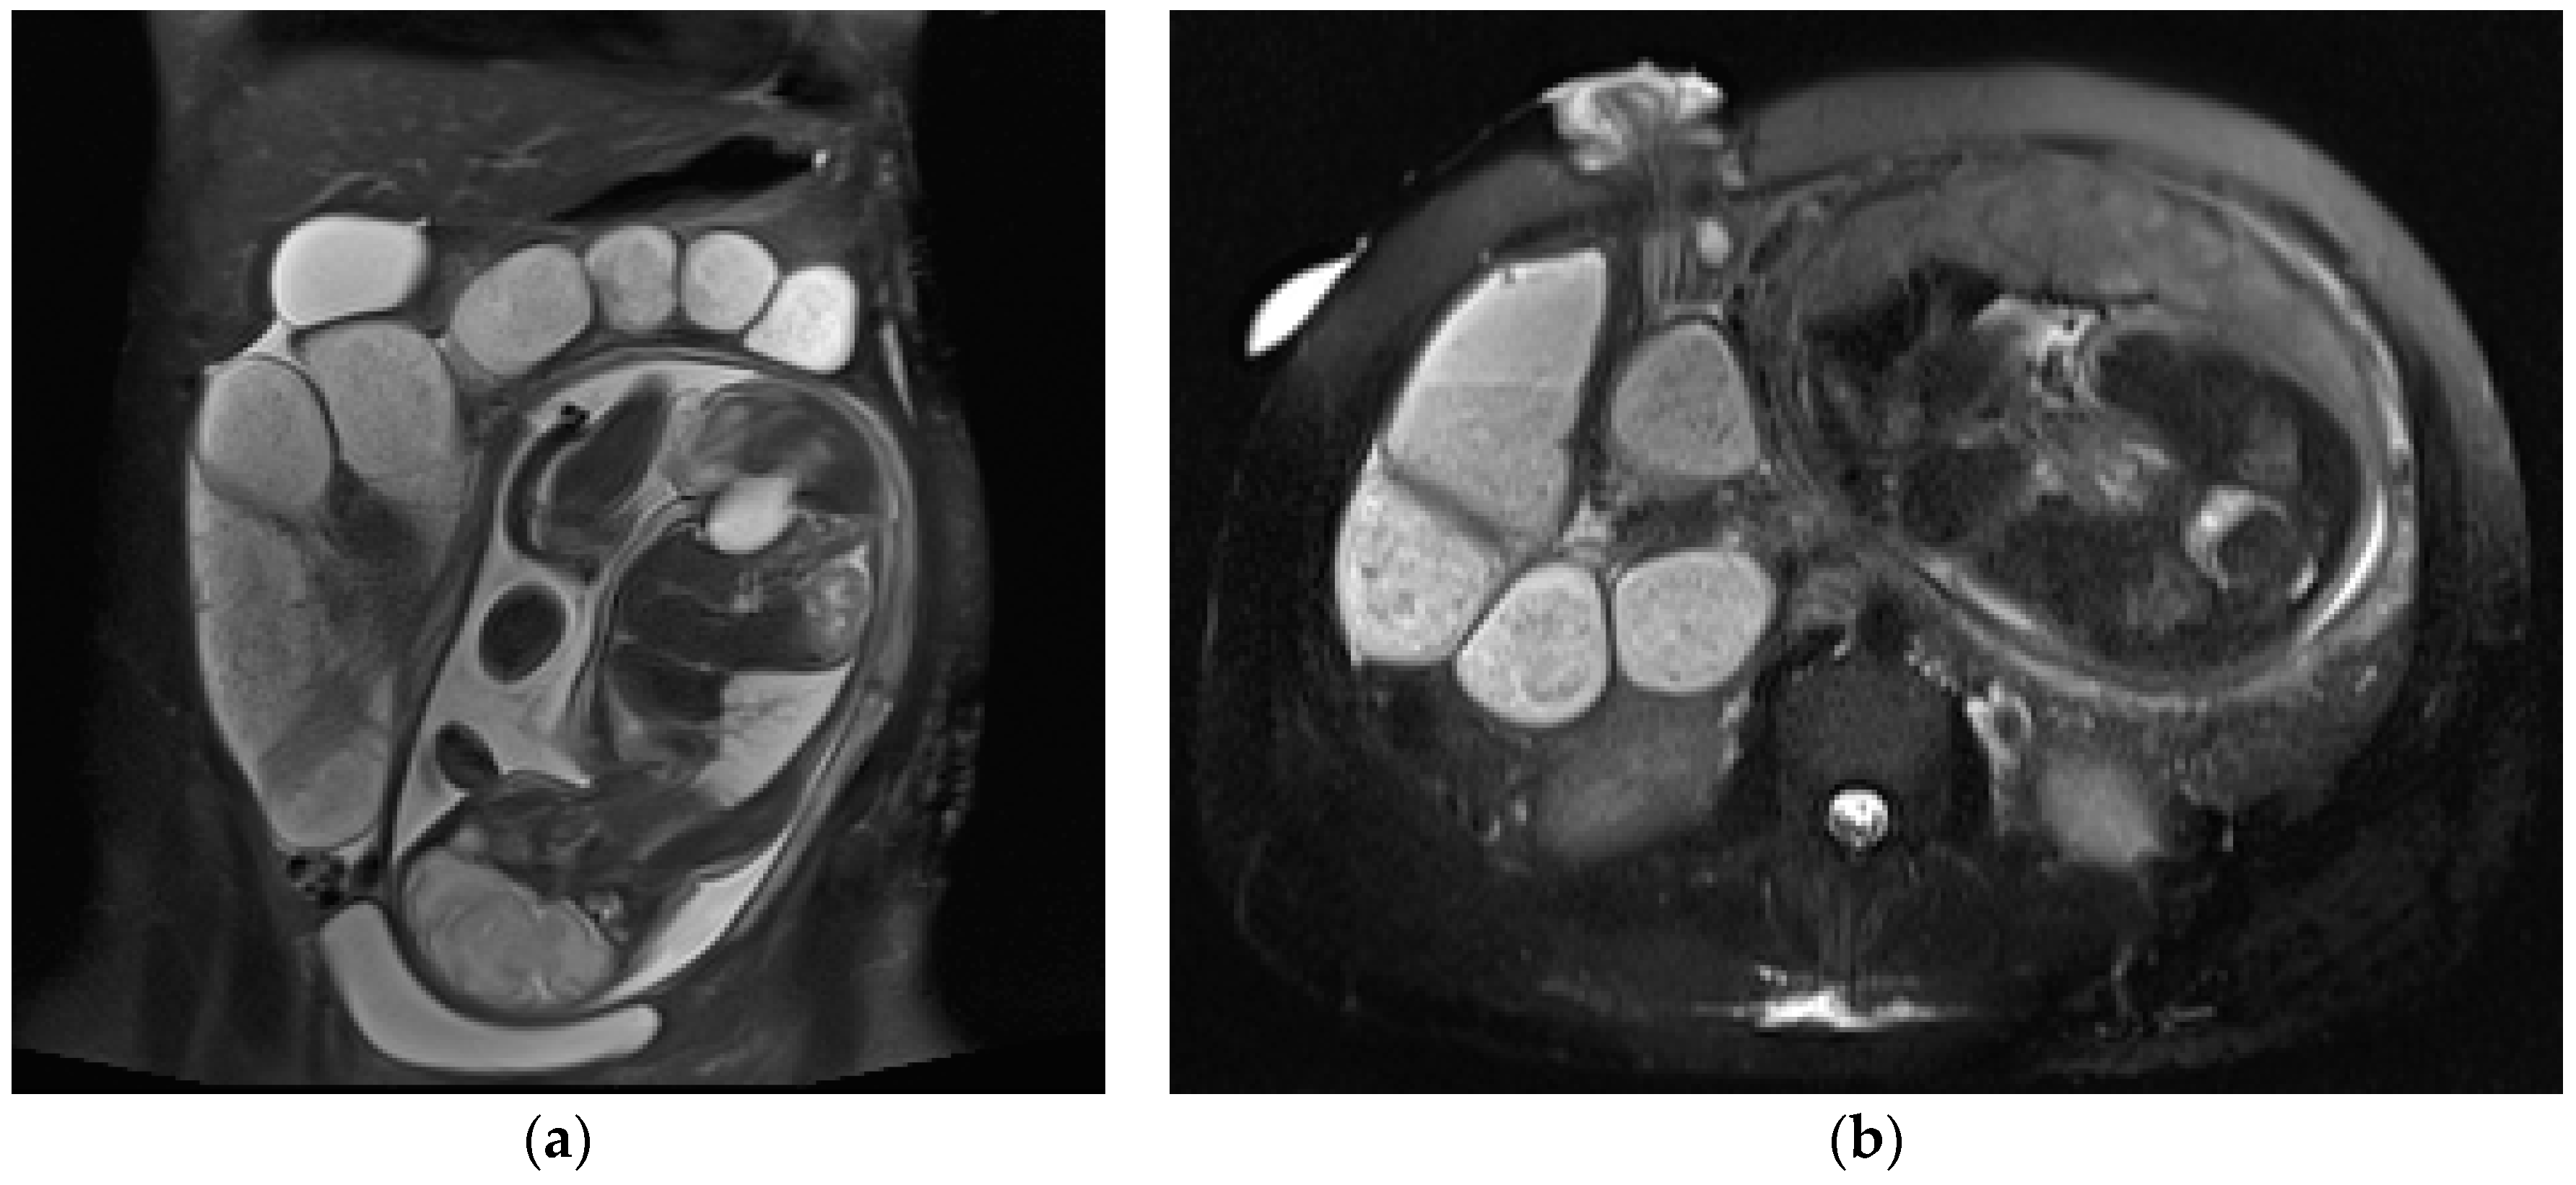

MRI demonstrates pancreatic enlargement and oedema, with reduced intensity on T1-weighted images and increased intensity on T2-weighted images (Figure 6).

Figure 6.

A 27-year-old pregnant woman with acute abdominal pain and elevated lipase levels (451 UI/mL). Coronal (a) and axial (b) T2-weighted sequences show peripancreatic fat stranding and fluid (arrows), interdigitating through pancreatic parenchyma. These findings are consistent with acute pancreatitis.